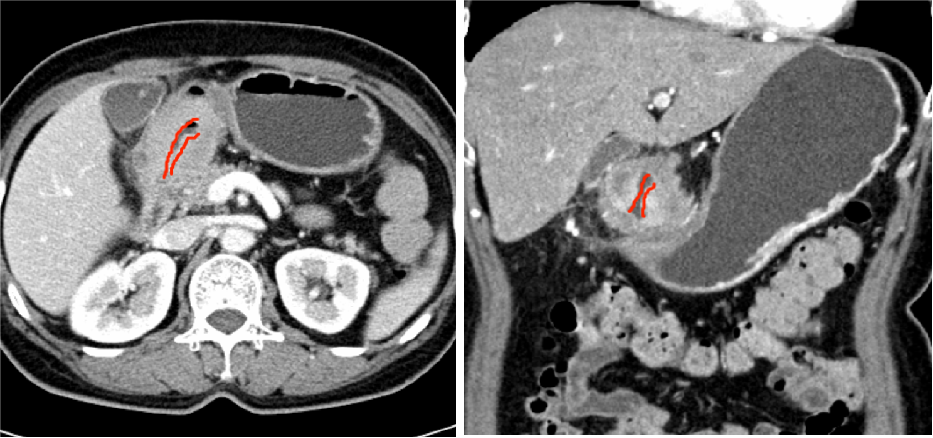

经过胃镜、CT等检查发现,周先生胃窦部有一个巨大肿块,已导致幽门梗阻,活检结果及影像学检查显示为“局部晚期胃癌”。

长期吃不下饭导致周先生全身营养条件差,暂时不具备手术条件。而且检查发现肿瘤伴胃周围多发淋巴结转移。如果按照传统的治疗方式,这种情况现阶段只能做一些保守治疗,无法达到根治。

“难道我连手术机会都没有了吗?”听到结果,周先生一度情绪崩溃。医生根据周先生的情况,为他制定了一套个性化治疗方案——先通过鼻饲管改善营养状况,再进行肿瘤的动脉灌注治疗联合免疫治疗。

三个疗程后,周先生的肿瘤和胃周围淋巴结明显缩小,为手术创造了机会,最终顺利切除肿瘤。